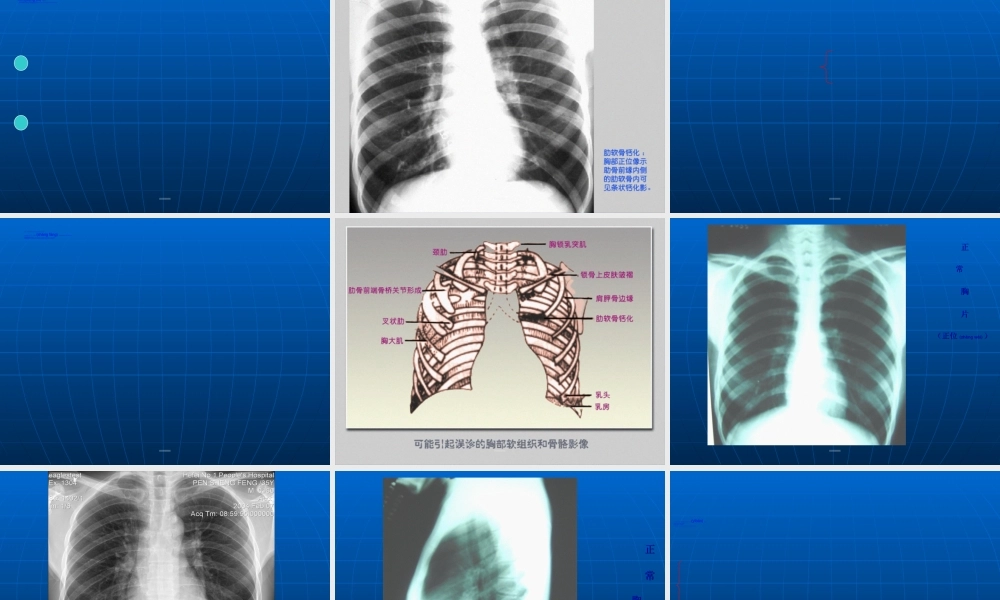

当X线穿过胸部时,由于两肺与其周围的胸壁、纵隔及横膈对X线吸收的差别,产生天然(tiānrán)对比影像,因此呼吸系统疾病应用X线检查较其他系统普遍。近年来,由于CT、MRI、DSA的临床应用,突破了普通X线诊断的限度。但普通X线检查在胸部疾病诊断中仍占主导地位。第第第第第第第第第第1.常规X线检查(jiǎnchá):(1)透视:首选(2)摄片:a.胸部正位片:后前位、前后位;立位、卧位b.胸部侧位片:左侧位、右侧位c.胸部斜位片:左前斜、右前斜d.前弓位片:显示肺尖及锁骨肋骨后方重叠的病变,中叶或舌叶不张,叶间胸膜积液。第第第第第第第第第第由于CT及MRI的应用,X线的一些如体层摄影,高千伏摄影,支气管造影检查已逐步淘汰(táotài),仅属于介入放射学范畴的肺动脉造影,支气管造影及经皮肺穿刺仍经常使用。第第第第第第第第第第2.CT检查:胸部CT扫描较普通X线检查的优越性:⑴密度分辨率高;⑵CT断面无影像重叠,病灶显示清晰;⑶适用于普通胸片表现正常,而临床高度怀疑胸、肺部病变。CT扫描一般用平扫,在需要观察病变与肺门、纵隔血管的关系(guānxì)时,及纵隔有无淋巴结转移时需增强扫描。第第第第第第第第第第3.MRI检查:对纵隔心大血管及胸壁病变有着(yǒuzhe)独特的优点,对肺实质病变效果较差。第第第第第第第第第第第第第第第第第第第第(zhèngcháng)正常胸部X线影像(yǐnɡxiànɡ)是胸腔内、外各种组织和器官的影像(yǐnɡxiànɡ)重叠,熟悉各种影像(yǐnɡxiànɡ)的正常及变异,是胸部影像(yǐnɡxiànɡ)诊断的基础。第第第第第第第第第第(xiōngkuò)包括软组织和骨骼,正常两侧对称。一、胸壁软组织:1.胸锁乳头肌及锁骨上皮肤皱褶:(1)胸锁乳头肌起自胸骨柄及锁骨胸骨端,斜向后止于乳突,在两肺尖内侧形成外缘锐利(ruìlì)、均匀致密的图像。(2)锁骨上皮肤皱褶系锁骨上皮肤及皮下组织的投照。表现为与锁骨上缘平行的3~5mm宽的薄层软组织影,其内侧与锁骨乳头肌影相连。略成直角。当肥胖者锁骨上窝不凹陷,或有肿块时不显影。第第第第第第第第第第第第第第第第第第第第2.胸大肌:于两侧肺野中外带可形成扇形致密影,下缘锐利,呈一斜线与腋前皮肤皱褶连续。一般右侧较明显,不可误认为病变。3.女性(nǚxìng)乳房及乳头:女性乳房可在两肺下野形成下缘清楚、上缘不清且密度逐渐变淡的半圆形致密影,其下缘向外与腋部皮肤连续,勿误认为肺炎。乳头在两肺下野相当与第5前肋间处,有时可形成小圆形致密影...